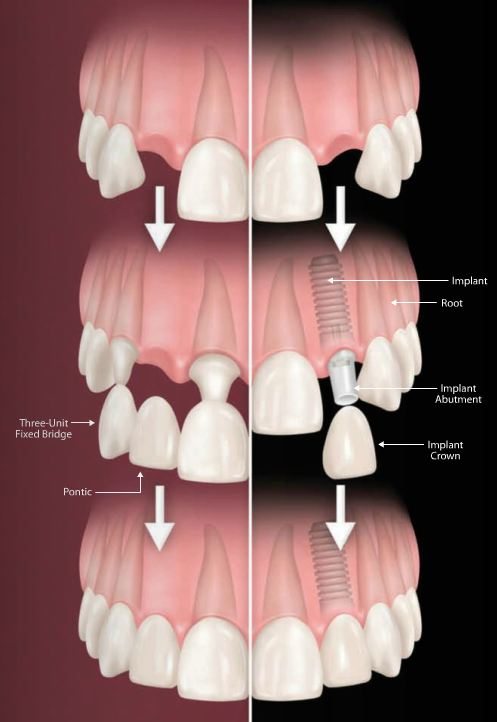

2. Trồng răng bắc cầu bằng sứ Emax Zirconia CAD/CAM

Phương án bắc cầu là mài 2 răng bên cạnh răng mất, sau đó làm cầu 3 răng sứ dính lại với nhau để phục hình lại răng mất cho thẩm mỹ và cố định. Phương pháp này giúp phục hồi chức năng ăn nhai tương đối. Vệ sinh phải cẩn thận vì có phần kẽ hở giữa nướu răng và răng mất. Thới gian khoảng 2-3 ngày là hoàn tất. Chi phí cho loại răng Emax Zirconia CAD/CAM- loại răng thích hợp để phục hình cầu răng sứ răng cửa- là 4,5 triệu/ răng. Ưu điểm của loại răng sứ này là không bị đổi màu nướu răng sau một thời gian dài sử dụng và sườn Zirconia rất chắc chắn, phù hợp với việc làm cầu răng.

Bên trái là trồng răng bắc cầu bằng sứ Emax Zirconia CAD/CAM và bên phải là phương án implant

Đây được cho là phương án phục hình tối ưu nhất vì có thể khôi phục chân răng bị mất bằng một trụ implant. Khi có implant trong xương hàm thì phần xương khu vực đó sẽ không bị tiêu đi và chức năng an nhai cũng được phục hồi tốt nhất. Với phương án này, các răng bên cạnh không bị ảnh hưởng gì. Chi phí implant hiện tại khoảng 20 - 30 triệu/ răng tùy vào thương hiệu implant. Thời gian trung bình khoảng 1 tuần đến 6 tháng tùy vào từng trường hợp cụ thể.